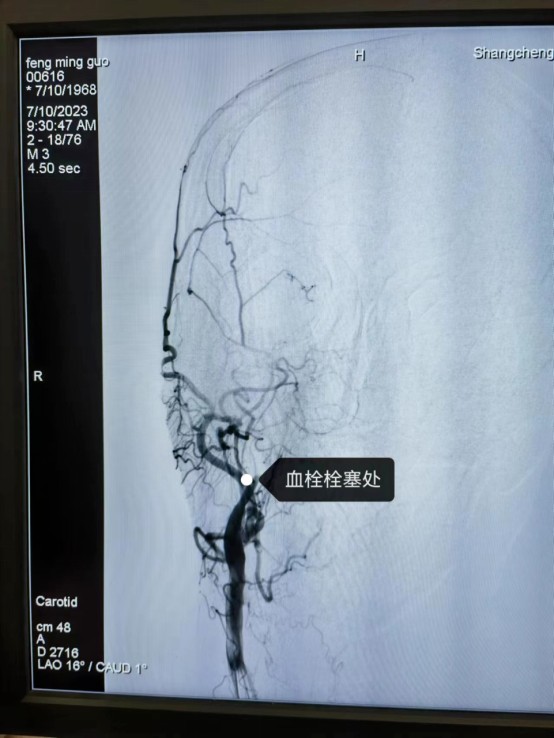

近日,55岁的冯先生突发急性脑梗死,我院卒中中心启动绿色通道,给予静脉溶栓桥接取栓治疗,成功打通堵塞的“生命管道”,患者转危为安,术后恢复良好,避免了“一人中风,全家瘫痪”的悲剧。

冯先生的成功救治,是静脉溶栓桥接动脉取栓治疗的完美结合。这次抢救工作的完美收官依靠的绝不仅仅是个人能力,它是整个团队共同努力的结果,检验了我院卒中中心对于脑卒中患者的快速鉴别诊断及多学科协作救治能力。我院卒中中心就是这样一支这样技术精湛、素质过硬的团队,在卒中介入治疗领域已经具备较强的综合实力,他们始终秉持着时间就是大脑、时间就是生命的理念,不断优化卒中急救模式和流程,为保障大别山区卒中患者能够得到及时、规范、有效的救治,降低县域卒中死亡率、致残率而不懈努力,为助力全面建设健康中国贡献自己的力量。